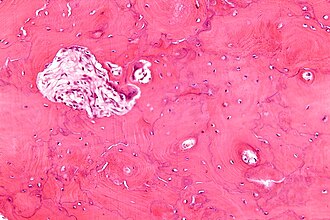

Paget's disease of the bone. H&E stain. | |

| LM | bone matrix has jigsaw-puzzle like pattern (jigsaw-puzzle pieces each ~ 100-500 micrometres in size in largest dimension), increased osteoclast activity |

- Bone matrix has jigsaw-puzzle like pattern.

- Jigsaw-puzzle pieces each ~ 100-500 micrometres in size (largest dimension).

- Increased osteoclast activity.